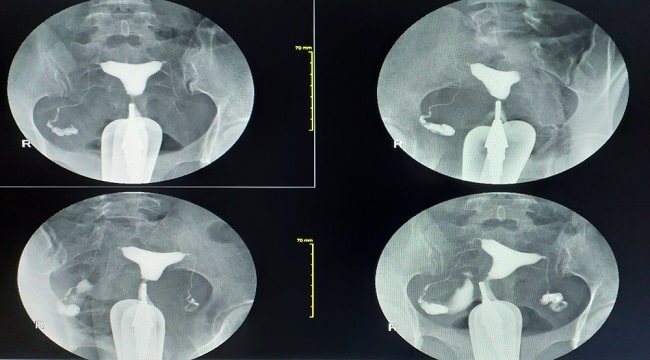

Histerosalpingografi, atau hysterosalpingography (HSG) adalah pemeriksaan radiografi untuk menilai uterus dan tuba falopi yang terutama digunakan untuk mengevaluasi infertilitas dan kelainan patensi tuba.

Kontraindikasi hysterosalpingography adalah kehamilan, hipersensitivitas terhadap medium kontras, dan penyakit radang panggul.Teknik HSG yang dilakukan dengan benar dapat mendeteksi patensi tuba, kontur kavitas uteri, dan lebar kanalis servikalis.[1,2]

Injeksi media kontras lebih lanjut akan memberikan gambaran tuba falopi (kornu, isthmus, dan ampula) dengan jelas dan derajat dari spillage. Komplikasi dari HSG adalah nyeri saat dan setelah prosedur dilakukan, reaksi alergi terhadap kontras, dan infeksi.[3,4]